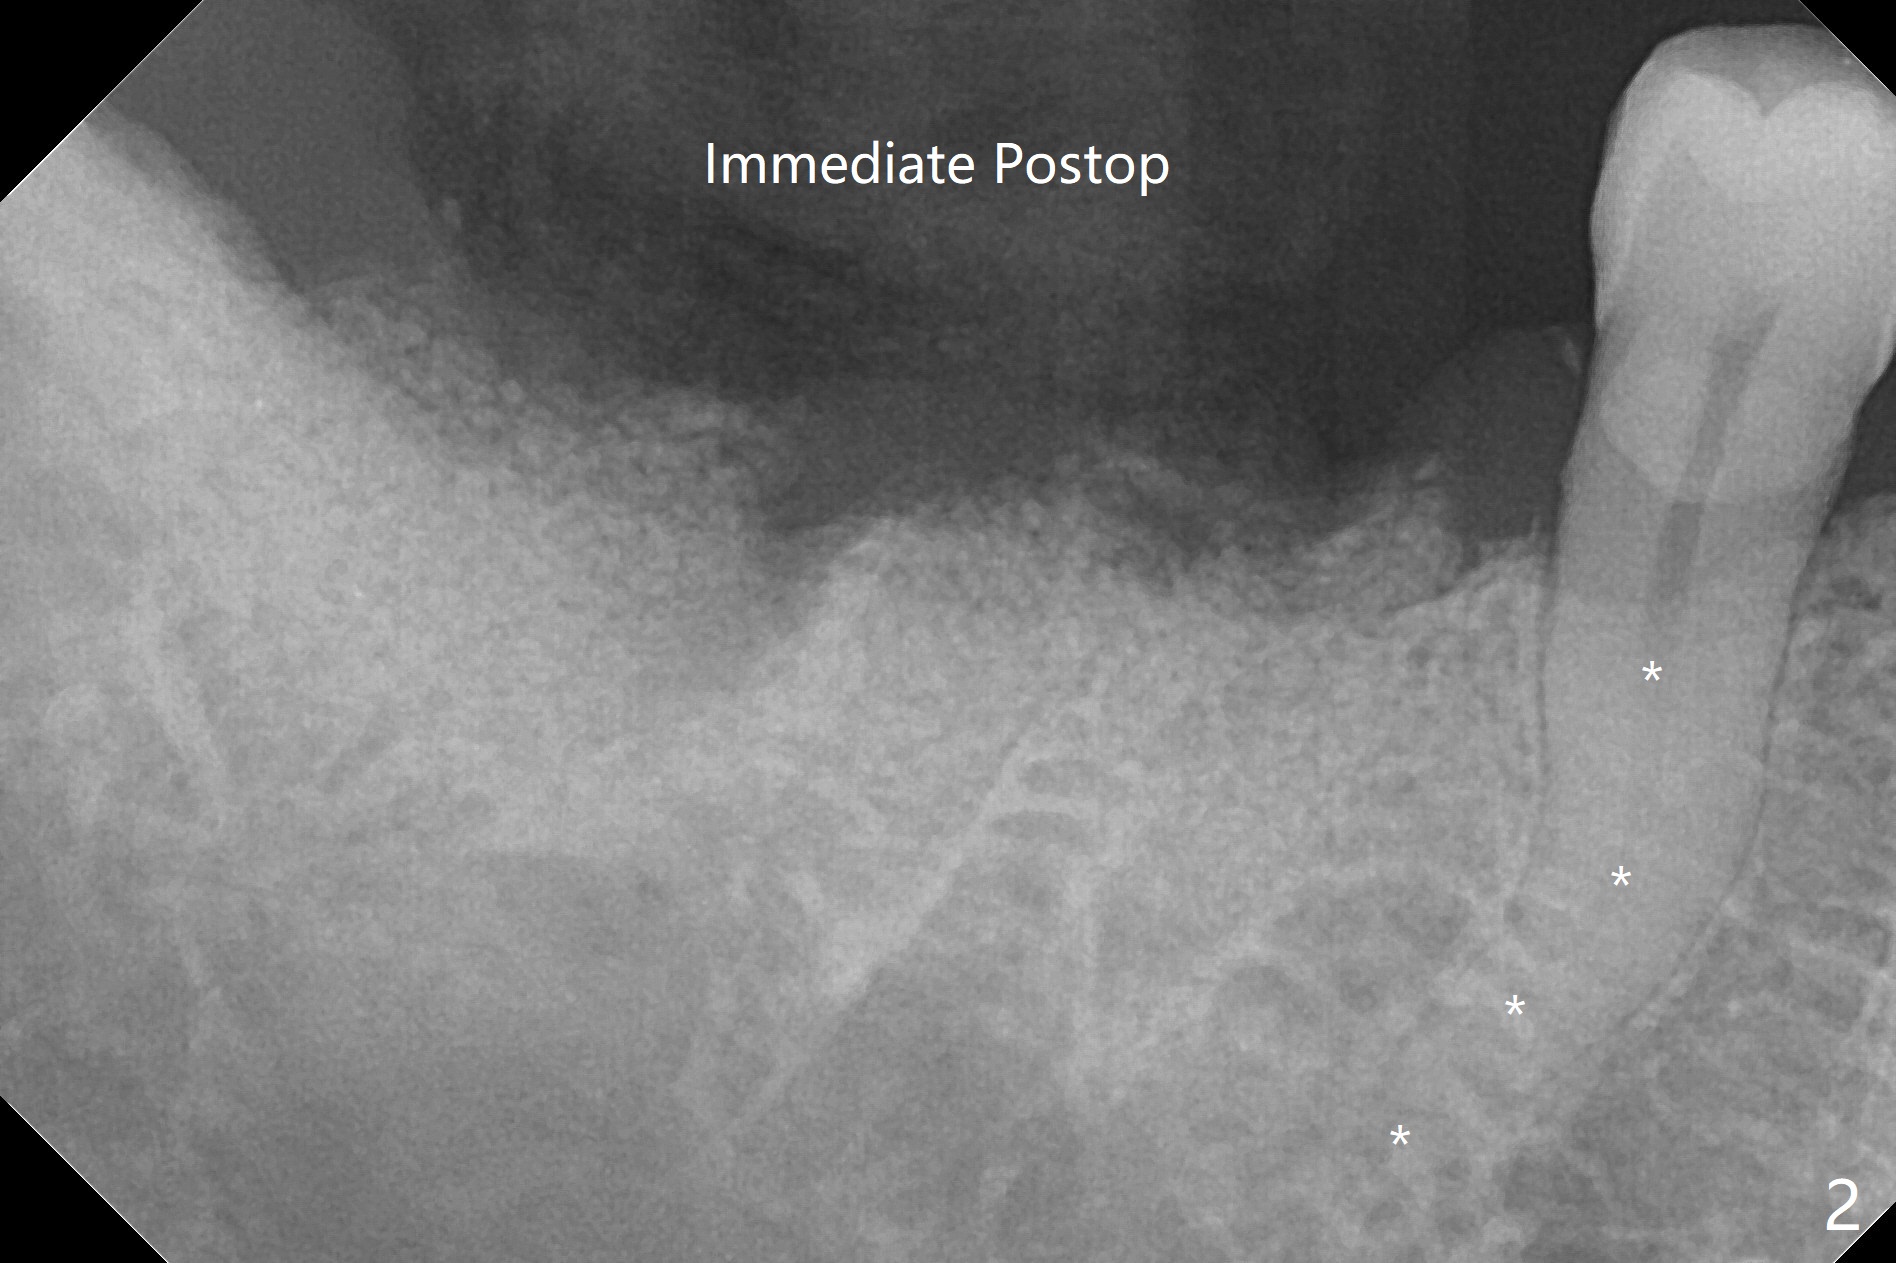

A 53-year-old man requests extraction of #30 and 31 post-SRP (Fig.1 (*: furca radiolucency). There is severe hemorrhage from the sockets post extraction, which makes bone graft difficult (Fig.2). Osteogen plug should have been used in stead of Ossogen. The socket openings are closed with 12x12 and 8x8 mm BioXclude and 4-0 PGA. The root curvature of the tooth #29 (Fig.2 *) suggests bruxism. The sockets heal 12 days postop (Fig.3). The septum at #30 (Fig.1 *) remains 6 months postop. Be wary of deviation off the septum during osteotomy. Bone density at #30 and 31 is high (1400-1700 units, Fig.5,6). Be careful of bone heat during osteotomy. It appears that cortical taps are pending.